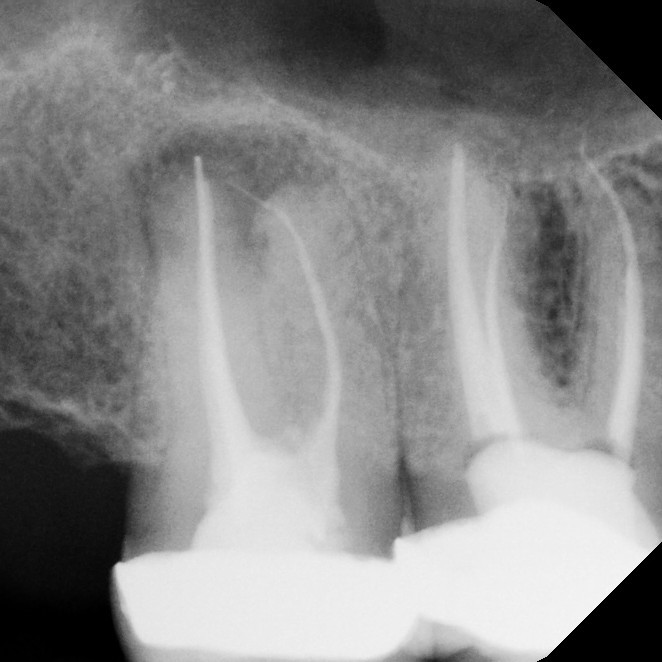

Root canal therapy is a specialized treatment designed to save a tooth that has been damaged by deep decay, trauma, or infection. Sometimes the problem causes noticeable pain or sensitivity, but in other cases it may develop quietly without obvious symptoms. During the procedure, the infected or damaged nerve tissue inside the tooth is carefully removed, the canals are disinfected, and the space is sealed to prevent further problems. Local anesthesia ensures you're completely comfortable throughout the process.

Thanks to advances in modern dentistry, root canals have become far more comfortable and efficient than they were in the past. Most patients report that the experience is comparable to having a standard filling, and recovery is typically quick. By treating the tooth promptly, you can avoid more serious dental issues, preserve your natural smile, and return to normal function without the need for extraction.